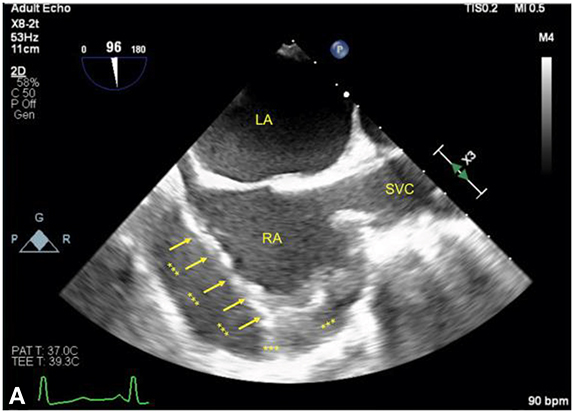

Figure 12.7.: Right Atrium (RA) Collapse from Early Cardiac Tamponade.

Right atrium (RA) collapse from early cardiac tamponade. The figures show the RA in the midesophageal bicaval view in the same patient with an acute pericardial effusion (labeled with asterisks). A. The RA is compressed by the effusion (arrows) in early ventricular systole as denoted by the ECG, corresponding approximately to the x-descent on a CVP waveform when the RA is most susceptible to compression. B. The RA in late ventricular systole is seen, corresponding to a point just before the V-wave, when the atrium is at its fullest just before tricuspid valve opening. LA, left atrium; SVC, superior vena cava.